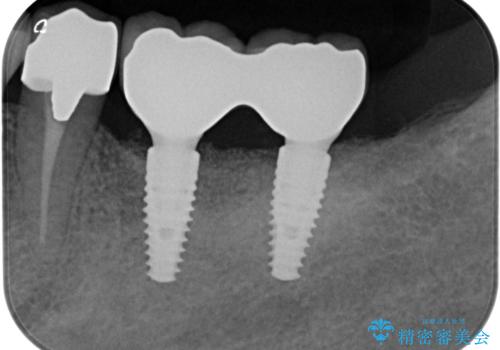

抜歯後、インプラントを用いて咬合機能を回復すると共に周囲に強固な角化歯肉を移植することによりより長期にわたり安定したインプラント周囲環境となるよう治療を計画します。

- 83.6万円(インプラント×2・アバットメント×2・クラウン×2)費用は治療当時の料金となります